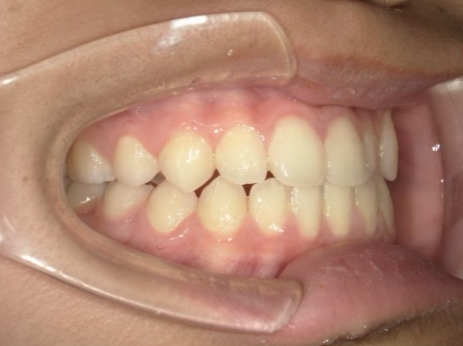

治療中④ 小4:10y1m

左上3が八重歯で萌出中